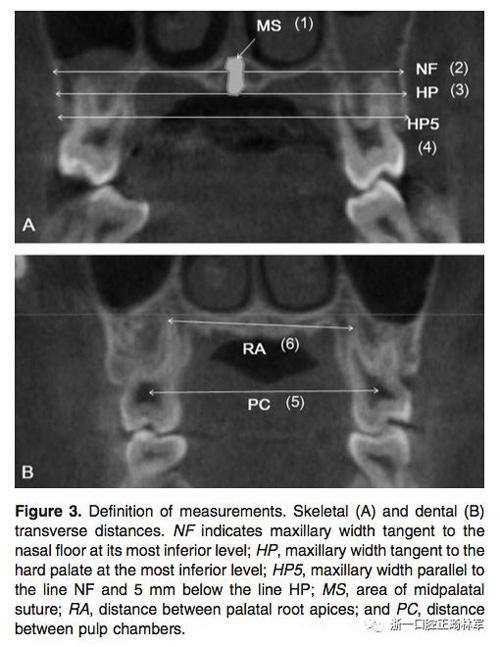

在治療前(T1)和擴弓后3個月(T2)拍攝CBCT,獲得的數(shù)據(jù)由In Vivo Dental(Anatomage,San Jose,Calif)分析。為了在T1和T2階段設置相同的參考平面,CBCT圖像沿著腭中縫(x平面)定向,平行于腭平面(y平面)并且與鼻底(z平面)相切(Figure 2)。在腭中縫處評估橫向骨骼擴張,并在三個不同的平面進行線性測量:鼻底,硬腭和硬腭以下5mm。在根尖和牙冠水平測量橫向牙齒擴張(Figure 3)。評估兩側的牙槽傾斜度,牙長軸,牙齒垂直高度和骨開裂等情況(Figure 4,5)。所有測量均在每個上頜前磨牙和磨牙區(qū)域進行。